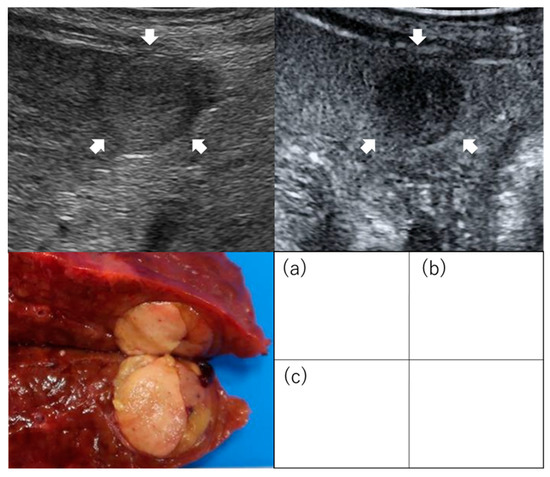

- Hatanaka, K.; Chung, H.; Kudo, M.; Haji, S.; Minami, Y.; Maekawa, K.; Hayaishi, S.; Nagai, T.; Takita, M.; Kudo, K.; et al. Usefulness of the post-vascular phase of contrast-enhanced ultrasonography with sonazoid in the evaluation of gross types of hepatocellular carcinoma. Oncology 2010, 78 (Suppl. S1), 53–59. [Google Scholar] [CrossRef]

- Nuta, J.; Shingaki, N.; Ida, Y.; Shimizu, R.; Hayami, S.; Ueno, M.; Fukatsu, K.; Itonaga, M.; Yoshida, T.; Maeda, Y.; et al. Irregular Defects in Hepatocellular Carcinomas During the Kupffer Phase of Contrast-Enhanced Ultrasonography with Perfluorobutane Microbubbles: Pathological Features and Metastatic Recurrence After Surgical Resection. Ultrasound Med. Biol. 2017, 43, 1829–1836. [Google Scholar] [CrossRef]